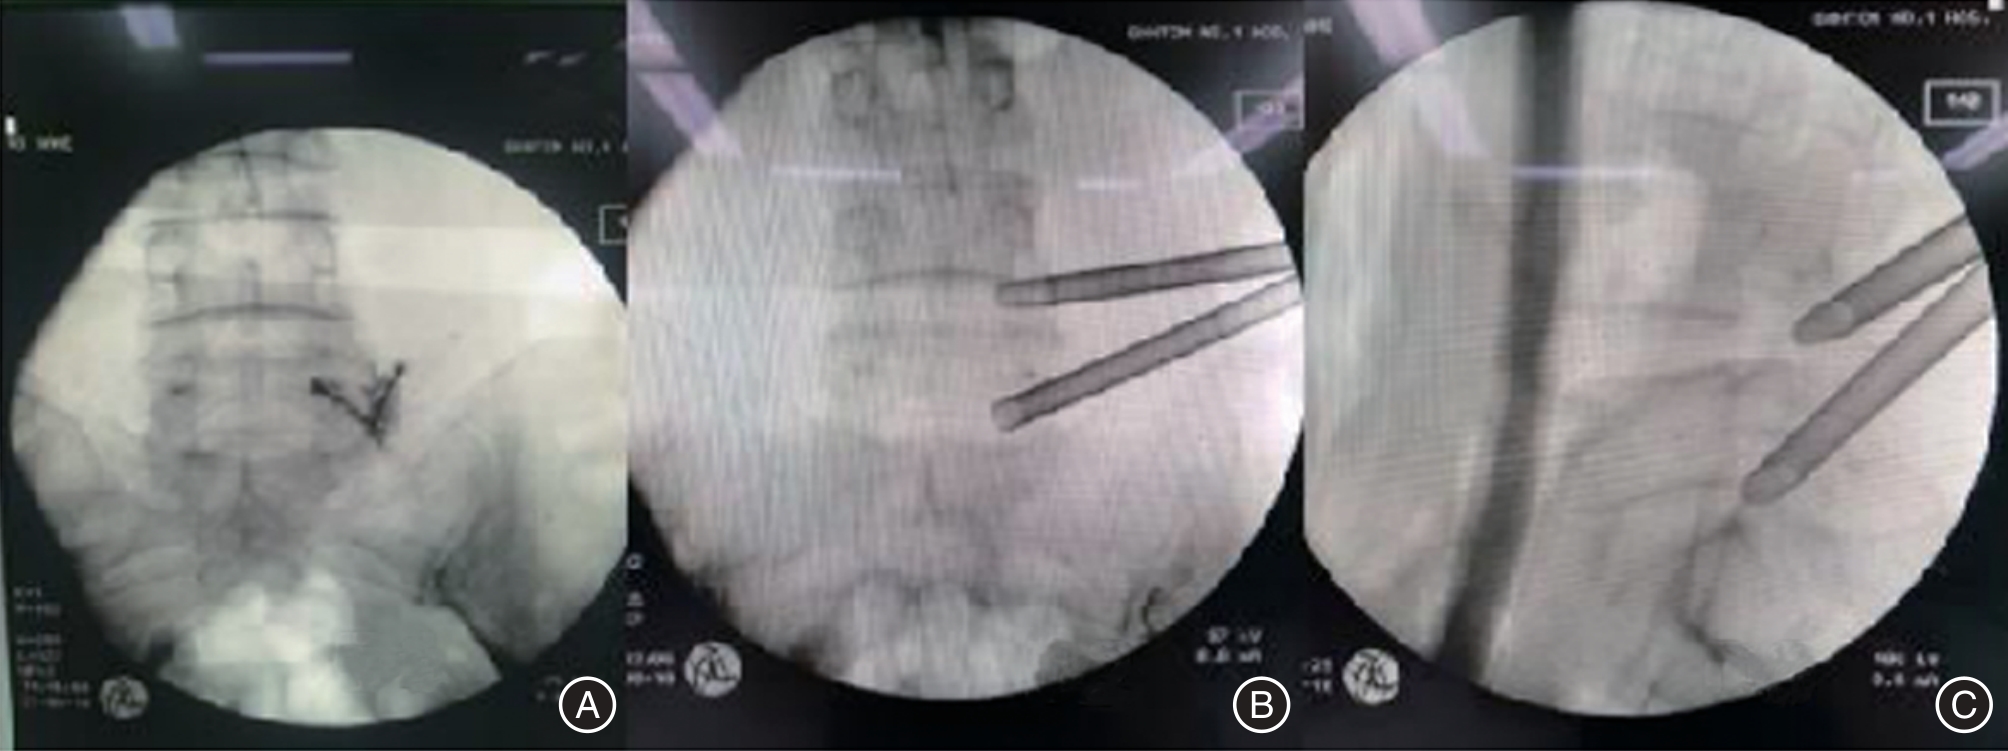

目的 探讨单一切口椎间孔镜治疗双节段腰椎管狭窄并腰椎间盘突出症的临床疗效。 方法 回顾性分析2016年3月至2018年5月在广西中医药大学第一附属医院脊柱骨伤科就诊的40例双节段腰椎管狭窄并腰椎间盘突出症患者临床资料,其中通过单一切口同时穿刺椎间孔镜治疗的患者11例(A组),通过单一切口前后穿刺椎间孔镜治疗的患者13例(B组),通过双切口前后穿刺椎间孔镜治疗的患者16例(C组)。记录患者的一般临床资料,三组不同时间点(术前、术后即刻、术后1周、术后1个月、末期随访)的VAS评分、JOA评分及临床疗效,并运用统计学进行分析。 结果 三组间手术时间、术中透视次数、皮肤切开长度和满意度差异均有统计学意义(P < 0.05);手术时间与手术方式在VAS、JOA评分上存在交互作用;手术时间、手术方式在VAS、JOA评分上存在主效应(P < 0.05);三组术后即刻、术后1周、术后1个月、末期随访与术前在VAS、JOA评分上比较差异均有统计学意义(P < 0.05);三组间术后即刻在VAS、JOA评分上差异有统计学意义(P < 0.05);三组间术后1周在VAS评分上差异有统计意义(P < 0.05)。 结论 单一切口椎间孔镜技术同时减压双节段腰椎管狭窄并腰椎间盘突出症的有效手段,具有手术时间短、术中透视少,损伤小等优势,患者满意,值得临床推广应用。

Objective To evaluate the clinical effectiveness of single?incision intervertebral foraminotomy in treating double?segment lumbar spinal stenosis accompanied by lumbar disc herniation. Methods A retrospective analysis was conducted on 40 cases of double?segment lumbar spinal stenosis and lumbar disc herniation treated in our orthopedic (spinal surgery) department from March 2016 to May 2018. Among these cases, 11 patients (Group A) were treated with percutaneous discectomy, 13 patients (Group B) underwent percutaneous endoscopic discectomy, and 16 patients (Group C) received double?incision percutaneous surgery. General clinical data for all patients were recorded. Visual Analog Scale (VAS) scores, Japanese Orthopaedic Association (JOA) scores, and clinical outcomes were assessed at five different time points: preoperatively, immediately postoperatively, one week postoperatively, one month postoperatively, and at the final follow?up. Statistical analysis was performed on the collected data. Results The operation time, the number of fluoroscopies performed on the hands, the length of the skin incision, and patient satisfaction were all statistically significant (P < 0.05). An interaction effect was observed between the operation time and the surgical procedure on both the VAS and JOA scores. Both the operation time and the surgical method had significant main effects on the VAS and JOA scores (P < 0.05). Significant differences in VAS and JOA scores were found among the three groups immediately post?surgery, one week post?surgery, one month post?operation, and at the end of the study (P < 0.05). Immediately after surgery, there were statistically significant differences in VAS and JOA scores among the three groups (P < 0.05). One week post?surgery, there were also statistically significant differences in VAS scores among the three groups (P < 0.05). Conclusions The single?incision intervertebral foramen technique is an effective approach for simultaneously addressing double?segment lumbar spinal stenosis and lumbar disc herniation through decompression. This method boasts a shorter operative duration, reduced intraoperative radiation exposure, and minimal tissue damage. Patient satisfaction is high, making it a valuable addition to clinical practice.